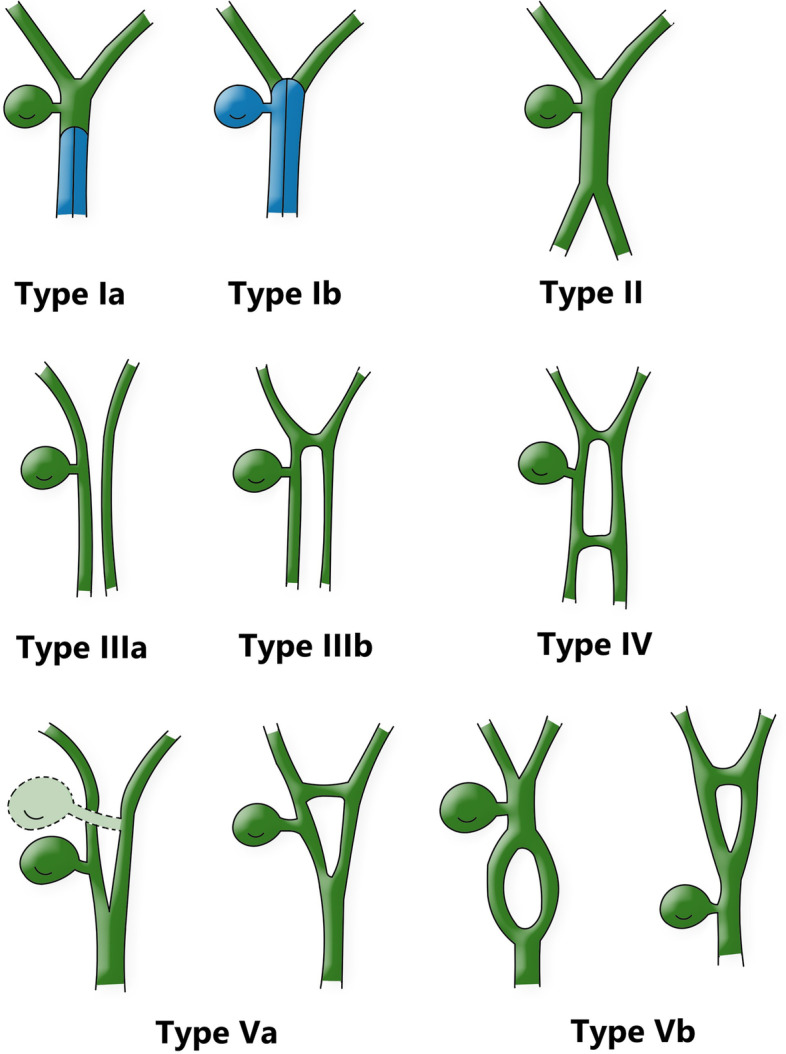

Duplication of the common bile duct is an extremely rare condition. The presence of double bile ducts is a normal step in human early embryogenesis. The definite lumen of the bile tree is developed by epithelial proliferation and vacuolization. As the vacuoles coalesce, they will initially create two parallel channels, which will gradually recede to form an isolated common anatomical structure of the common bile duct [ref. 4]. Regression failure of the double biliary system is considered to be the mechanism of type I anomaly [ref. 5].Chance elongation and early subdivision of the primitive hepatic furrow may be responsible for the other types of DCBD [ref. 6].The latest classification system of the DCBD proposed by Choi et al. [ref. 7] (2007) based on morphology which did not take into account of the aberrant CBD exits. They described five subtypes involving seven variants (Fig. 3). Since then, three new variants of double common bile duct were reported consecutively, however, none of these were classified into classification system [ref. 8–ref. 11] (Fig. 4). Our case is a new variant of diaphragmatic common bile duct duplication type I.The reason that why our case was classified as type I was that it was confirmed intraoperatively that there was a septum in common bile duct rather than two separate common bile ducts. The septum of original type I was located in the common bile duct. In our case, the septum in the common bile duct extended to the junction of the left and right hepatic ducts. The above-mentioned variants need a comprehensive classification to encompass these newly discovered variants. Thus, our classification system is as follows (Fig. 5): Type I, Partially (a) or completely (b) septum within the lumen; Type II, the distal bile duct bifurcates to two independent drainages; Type III, double biliary drainage without any communication (a), with intrahepatic communication (b); Type IV, double biliary drainage with extrahepatic communicating channels; TypeV, duplicated commen bile ducts join as a single biliary drainage channel,the gallbladder is attached to the repeated biliary ducts or Left or right hepatic duct (a), the gallbladder is connected to the common bile duct before or after separation(b). Our classification is including all types of common bile duct duplication reported in the present literature. Because of the location of the gallbladder junction and the location of the traffic between the repeated biliary ducts, our classification may contain additional variations not found.